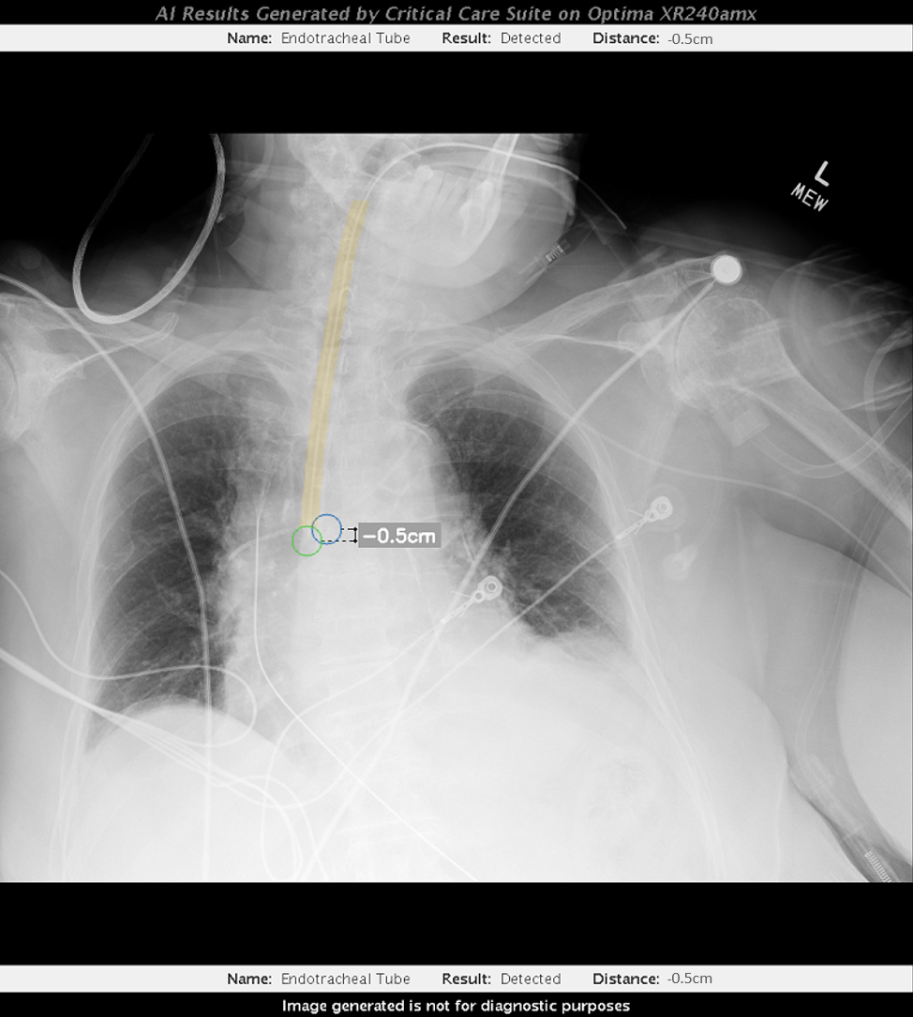

Bằng cách kết hợp AI vào hệ thống chăm sóc sức khỏe, chúng ta cho phép sử dụng thiết bị y tế theo cách thông minh hơn, đồng nghĩa với việc có thể thăm khám cho nhiều bệnh nhân hơn và mắc ít sai sót hơn. Công nghệ AI cũng giúp chẩn đoán tốt hơn bằng cách luôn luôn diễn giải chẩn đoán theo cách hợp lý nhất. Do đó, nó cho phép các bác sĩ chẩn đoán hình ảnh có thể kịp thời xác nhận kết quả chẩn đoán.

Một lợi ích khác là AI có thể sắp xếp mức độ ưu tiên cho các hình ảnh chẩn đoán cần xem xét trước trong bối cảnh bùng nổ dữ liệu. Cụ thể, khi phòng cấp cứu đang đông kín bệnh nhân, AI có thể hỗ trợ xác định hình ảnh chẩn đoán nào cần phải đọc trước, qua đó xác định người bệnh nào cần được ưu tiên điều trị. Một hệ thống hình ảnh y tế sử dụng AI có thể tự động phát hiện các vấn đề của một bệnh nhân và ưu tiên cho bệnh nhân đó được chăm sóc khẩn cấp. Nếu không có AI, y bác sĩ phải xử lý từng ca bệnh một và nếu có nhiều ca bệnh dồn lại, sẽ làm giảm cơ hội cấp cứu của người bệnh.

Bằng cách triển khai công nghệ y tế tích hợp AI, hệ thống y tế Việt Nam có thể cho phép truy cập kết quả chẩn đoán hình ảnh nhanh hơn. Công nghệ AI cũng có thể giúp nâng cao kỹ năng và năng suất của người dùng, nhờ đó khắc phục khó khăn của tình trạng thiếu hụt nhân viên y tế.

GE Healthcare có kế hoạch ra mắt các ứng dụng AI, đóng góp vào sự phát triển của ngành y tế tại Việt Nam. Cụ thể, một số thiết bị tích hợp AI dự kiến sẽ có mặt tại thị trường này từ năm tới. Nhìn chung, tất cả ứng dụng hỗ trợ AI mới của chúng tôi sẽ cải tiến những tính năng như chất lượng hình ảnh tốt hơn và kết quả chẩn đoán chính xác hơn xuyên suốt toàn bộ danh mục công nghệ hình ảnh y khoa.

Có một số công đoạn cần thực hiện trước khi chẩn đoán hình ảnh, bao gồm điều chỉnh tư thế của bệnh nhân, định vị dữ liệu, lập kế hoạch khám… GE chỉ đơn giản hiện thực hóa ý tưởng tích hợp AI vào các phương thức. Chúng tôi triển khai AI để cải thiện những công đoạn trước khi chụp và ứng dụng học sâu xuyên suốt toàn bộ quá trình chụp để tạo ra hình ảnh chất lượng tốt hơn. Trên thực tế, GE đã tập trung nỗ lực để tích hợp AI vào từng giai đoạn trong một lần khám.